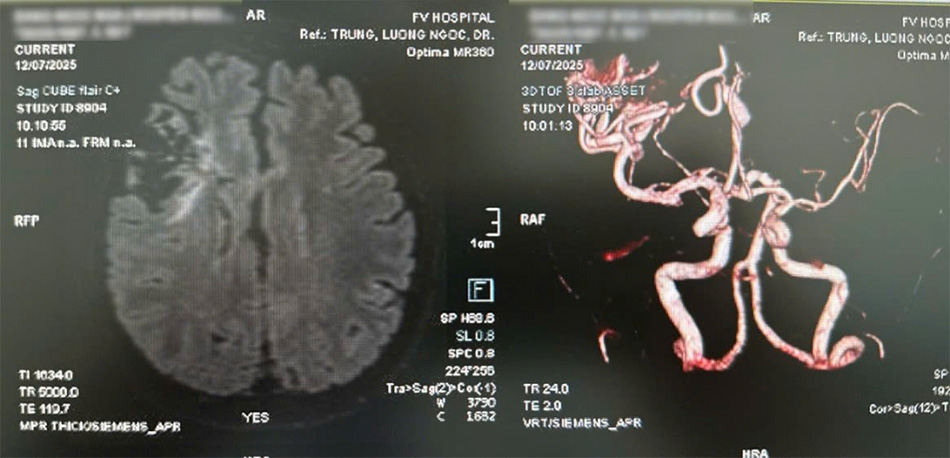

Tuy nhiên, khi thực hiện xét nghiệm MRI não để tầm soát di căn lại hé lộ một “quả bom nổ chậm” khác: trong não chị có một khối dị dạng mạch máu khổng lồ, chúng có thể vỡ bất cứ lúc nào, đặc biệt nguy hiểm khi gây mê phẫu thuật.

Hình chụp CT phình (hình trái) và khối dị dạng mạch máu não kích thước lớn (hình phải)